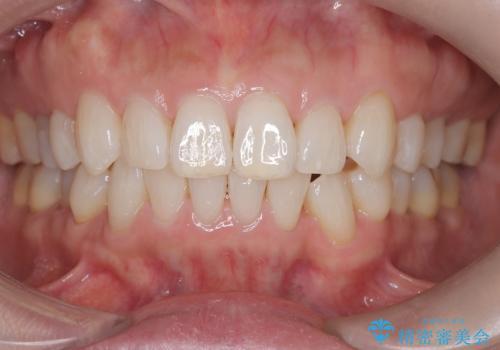

インビザラインで非抜歯矯正|ゴムかけで下顎犬歯の低位を改善し、噛み合わせも最適化

治療はインビザライン(マウスピース矯正)を使用し、歯列全体を計画的に移動させながら、下顎犬歯の低位をゴムかけによって徐々に引き上げました。患者様にはゴムの装着をしっかり継続していただき、順調に改善が進行。最終的に奥歯の噛み合わせも安定し、全体の咬合バランスが整いました。治療後は「自然な噛み心地になり、見た目も満足」と患者様にも喜んでいただきました。